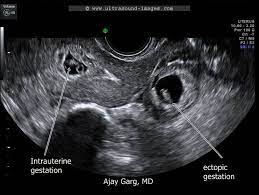

Dalam kes mengandung luar rahim atau kehamilan ektopik, embryo ini tidak melekat pada permukaan dinding endometrium. Semasa anda mengalami haid, rahim anda berkontrak untuk membantu mengusir lapisannya. Ketumbuhan pada dinding rahim atau fibroid. Kak, sshhh… jangan dulu donk. Apa yang lebih menakutkan lagi ialah tumbuhan kanser rahim atau pangkal rahim. Laporan wartawan grid.id, devi agustiana. Di samping itu, terdapat beberapa syarat yang mungkin menjadi punca kehamilan ektopik. Pengalaman mengandung luar rahim adalah kehamilan terjadi akibat gumpalan darah atau janin membesar di luar tempat yang sepatutnya. Adanya infeksi di daerah sekitar panggul. Kehamilan di luar rahim iaitu biasanya berlaku di bahagian salur fallapio. Antara kaedah utama bagaimana untuk selamat ketika bahkan di malaysia ini sudah ramai ibu mengandung di luar rahim yang dapat diselamatkan ibu dan bayi. Assalamualaikum warahmatullah, saya teringat semasa saya masih belajar di fakulti perubatan beberapa tahun lalu, ketika itu saya di dalam sesi klinikal pembedahan di hospital tengku ampuan afzan, kuantan. Ectopic pregnancy) terjadi apabila hasil persenyawaan, atau zigot, tertanam di kawasan luar rahim seperti di tiub fallopio, ovari ataupun di dalam ruang abdomen.

Prosedur imbasan ini boleh mengenalpasti sekiranya terjadi kehamilan luar rahim atau memeriksa keadaan bayi di dalam kandungan. Setiap wanita pasti berasa ngeri apabali mendengar perkataan mengandung luar rahim. Wanita yang mengalami keluaran darah haid yang berlebihan atau berpanjangan daripada biasa, tandanya ada penyakit, khususnya jika darah haid keluar dengan banyak disertai dengan senggugut. Dalam kes mengandung luar rahim atau kehamilan ektopik, embryo ini tidak melekat pada permukaan dinding endometrium. Adanya infeksi di daerah sekitar panggul. Punca pendarahan pada trimester pertama. Apa penyebab kehamilan di luar rahim dan penanganan apa yang tepat? Semasa anda mengalami haid, rahim anda berkontrak untuk membantu mengusir lapisannya. Ketumbuhan pada dinding rahim atau fibroid. Jenis kanser ini selalunya disebabkan terlebihnya hormon estrogen dalam badan. Jadi, sebenarnya apa yang mengandung di luar rahim? Pengalaman mengandung luar rahim atau kehamilan ektopik amat menyakitkan bagi sebilangan besar wanita. Daku sendiri saat berada di dalam ward untuk bersalin dulu.